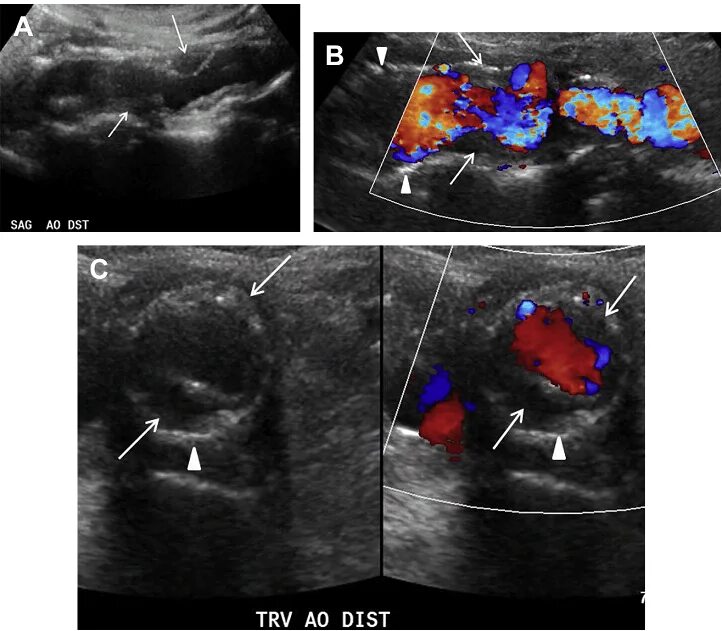

Атеросклероз на узи